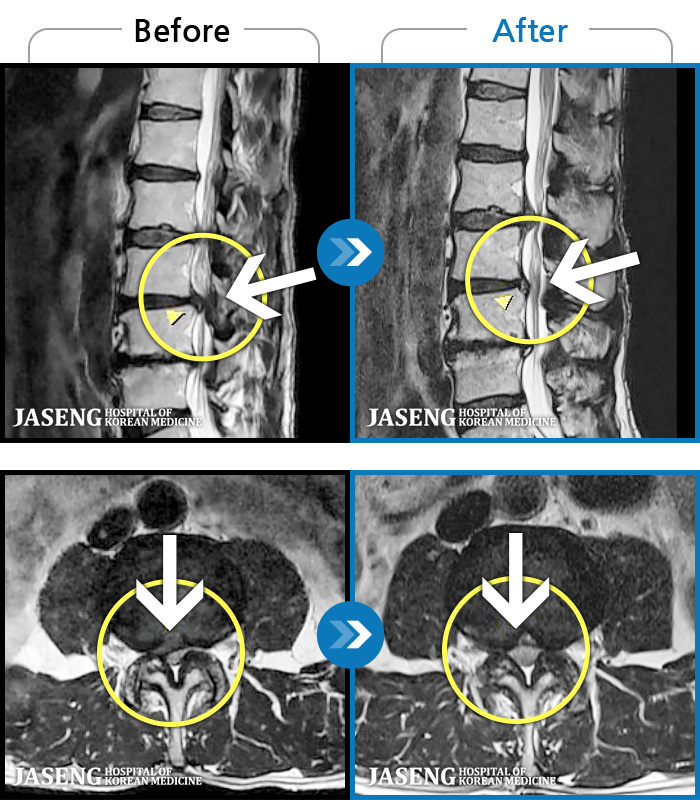

허리디스크

광주 · 장영우 원장

허리 우측 골반 통증, 우측 다리 저리고 엄지발가락 마비 증상

촬영시기

2019.11.05 ~ 2020.05.23

2020.05.29